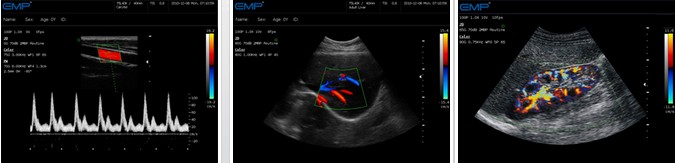

● 组织谐波成像(THI)——消除近场伪像和旁瓣干扰,使组织器官边缘成像更清晰

● 连续动态聚焦(CDF) ——显著提高探测深度和远中近场分辨率,给图像带来质的变化

● 方向能量图(PDI) ——血流成像更简便敏感,是检测血管疾病的有效手段

● 彩色多普勒(CFM) ——实时无创显示区域血流信息,检测客观精确

● 频谱多普勒(CW/PW) ——PW准确分析定点血流速度,精确提供距离分辨力;CW实时测量高速血流,优越的速度分辨力

● 敏感的血流测量 ——优秀的超低速血流检测技术,精度高,用时短

临床图像